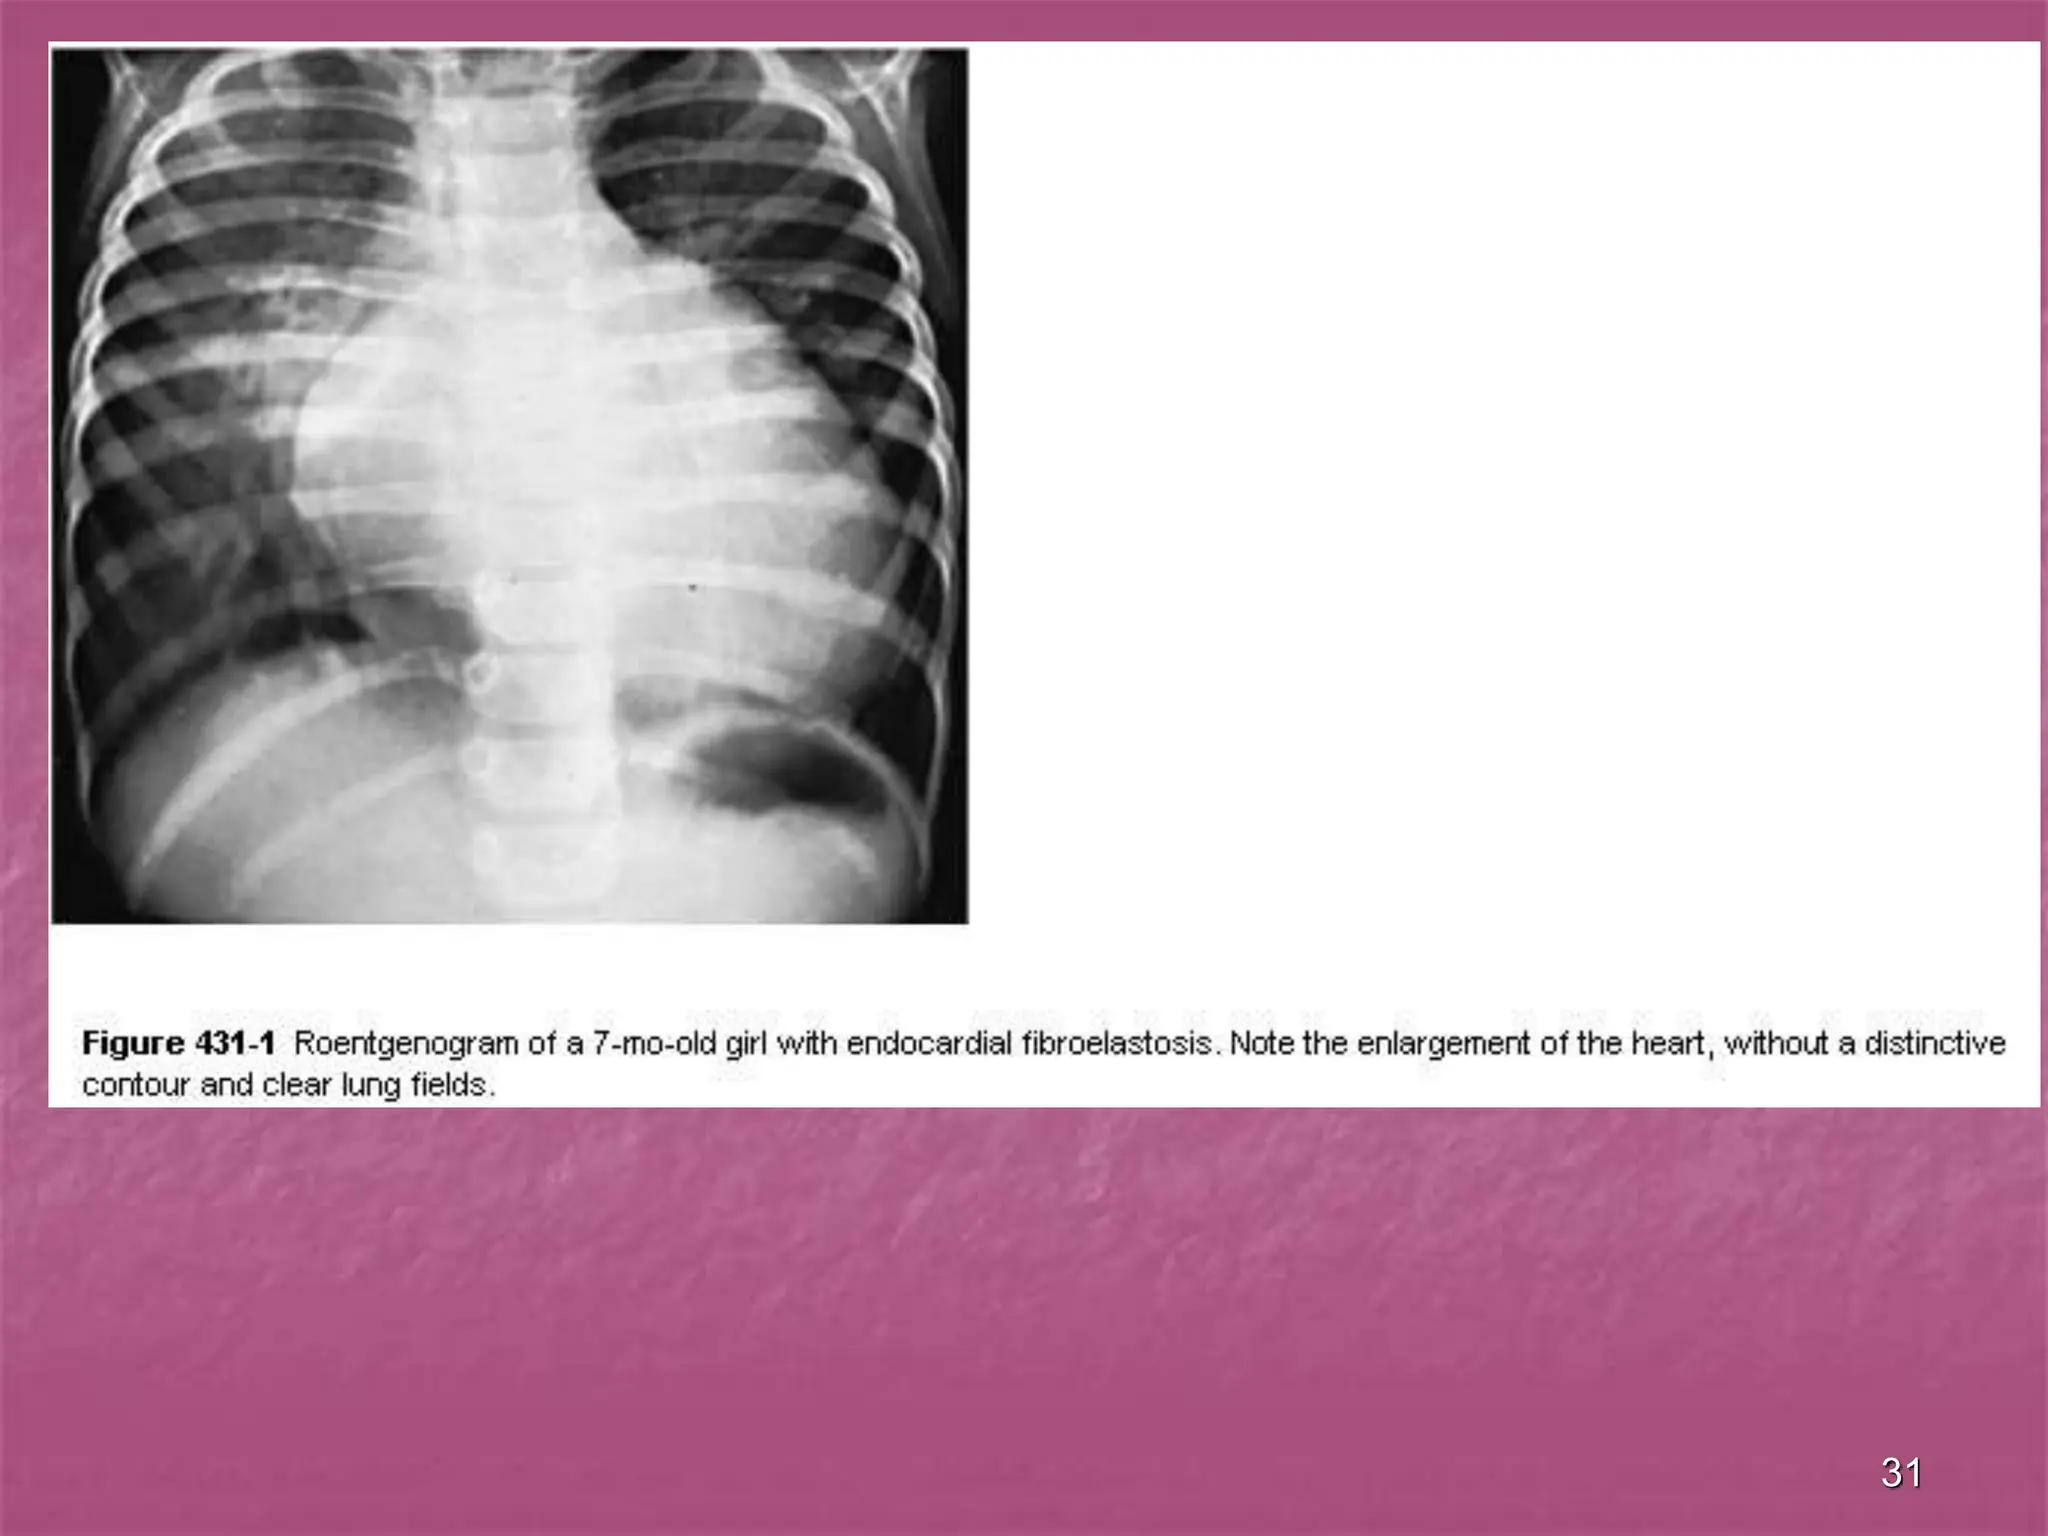

 Roentgenograms confirm significant

cardiac enlargement.